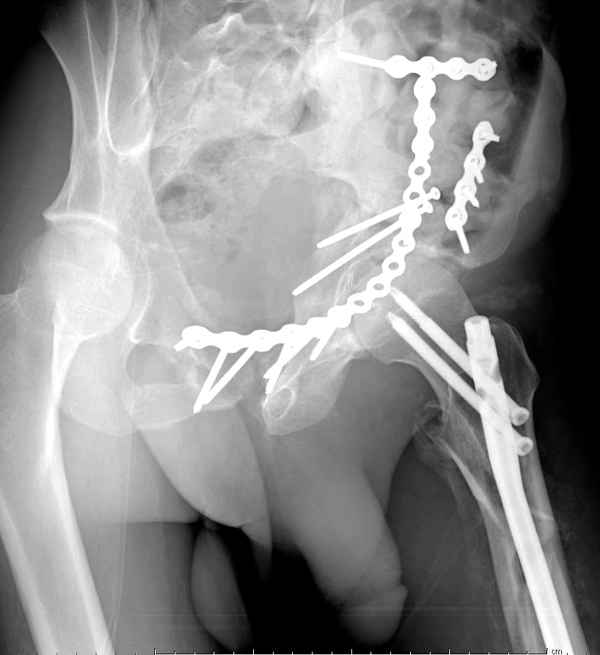

Все выступающие коллеги высказались насчет необходимости стандартных снимков по Judet, потому что для определения тактики лечения переломов вертлужной впадины 3Д снимки малоинформативны.

Летурнель разработал классификсацию на основании прямого, запирательного и подвздошного рентген снимков, котоые, кроме описания характера переломов, также подсказывают адекватный доступ для репозиции перелома.

Из того минимума, что представлено, мне кажется, мы имеем дело с двухколонным переломом вертлужной впадины. Обычно медиальный (центральный) "вывих" головки встречаются в сложных двухколонных переломах со смещением.

Здесь несколько вариантов двухколонных свежих переломов, которые были оперированы из одного-заднего, а также из двух: переднего и заднего доступов.